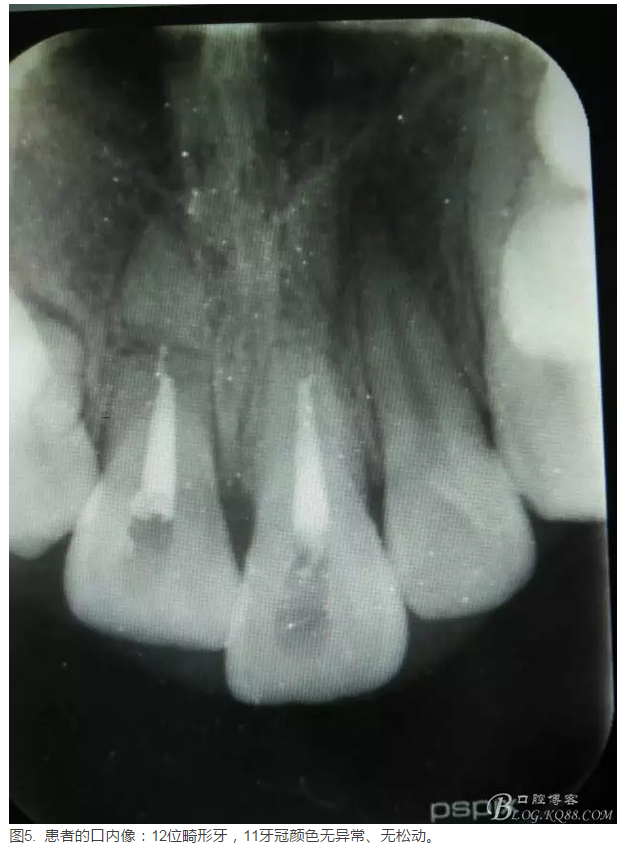

患者、李xx、男、15歲,主訴:牙不齊,矯正牙齒。??茩z查:發(fā)現(xiàn)11、21根尖三分之一折斷,患者否認有外傷史。正畸科治療建議如圖1.。術(shù)前簽手術(shù)同意書。